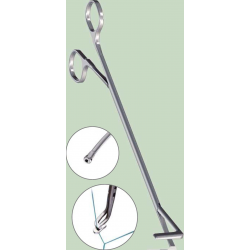

O Sistema de Trombectomia AngioJet permite a remoção percutânea de trombos

localizadas em artérias e veias periféricas, pontes de safena, artérias coronárias e condutos de acesso AV nativos ou sintéticos. A trombectomia é realizado com jatos de solução salina de alta pressão contidos na haste do cateter. O jatos de solução salina criam um efeito de baixa pressão para atrair o trombo para o cateter, fragmentar

o trombo e remova o trombo do local de tratamento. O sistema consiste de um conjunto de trombectomia de uso único (vários modelos disponíveis) e um consola móvel.

Mecanismo de Ação

1. O Console AngioJEt monitora e controla o sistema.

2. O Console energiza a bomba, que envia solução fisiológica pressurizada para a ponta do cateter.

3. Os jatos de solução fisiológica viajam para trás para criar uma zona de baixa pressão causando um efeito de vácuo. (Imagem 1)